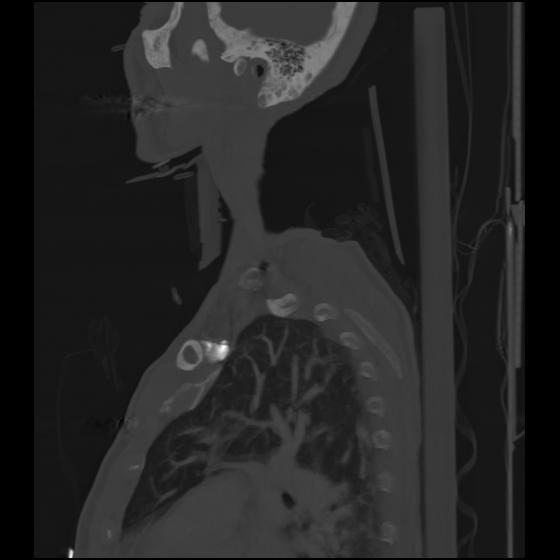

24 ANGIO,CE,Sag-MIP,5.000,ANGIO,Sag-MIP,